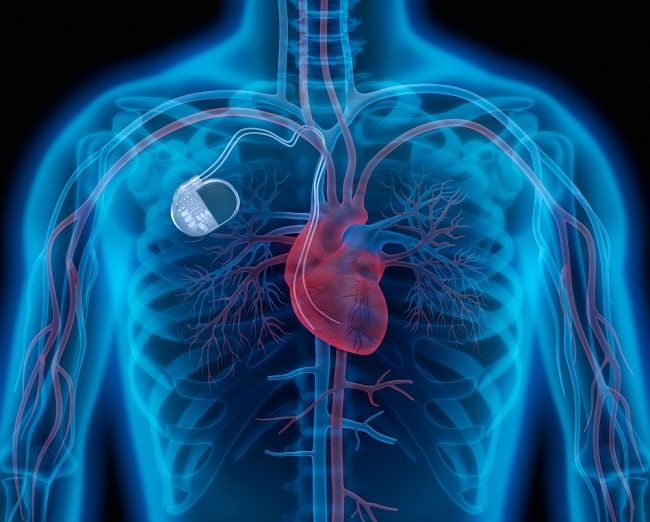

Envelope antibiotic diberikan pada saat implantasi alat elektronik kardiovaskular implan (ALEKA). Envelope antibiotic akan menyelimuti ALEKA dan dikembangkan untuk memegang alat sehingga menghasilkan lingkungan yang lebih stabil dan untuk menurunkan risiko infeksi dengan mengeluarkan antibiotik konsentrasi tinggi dalam jangka waktu lama yang efektif untuk melawan patogen umum pada ALEKA.

Ada 2 jenis envelope antibiotic ALEKA yang digunakan di Amerika Serikat dan keduanya bersifat absorbable. Satu terbuat dari absorbable multifilament block copolymer yang dilapisi polimer yang mengandung minocycline dan rifampicin. Satu lagi terbuat dari decellularized, non-crosslinked extracellular matrix (ECM) yang berasal dari submukosa usus babi yang dihidrasi dengan larutan gentamicin sebelum implantasi.[10]

TYRX Absorbable Antibacterial Envelope® adalah jenis envelope pertama yang terdiri dari selimut sekali pakai yang didesain untuk menahan ALEKA ketika alat dipasangkan ke badan. Selimut ini dibuat dari mesh multifilamen yang mengandung minocycline dan rifampicin. Selimut ini akan melepaskan antibiotik ke jaringan lokal selama setidaknya 7 hari dan akan diserap sempurna dalam kurang lebih 9 minggu.[2]